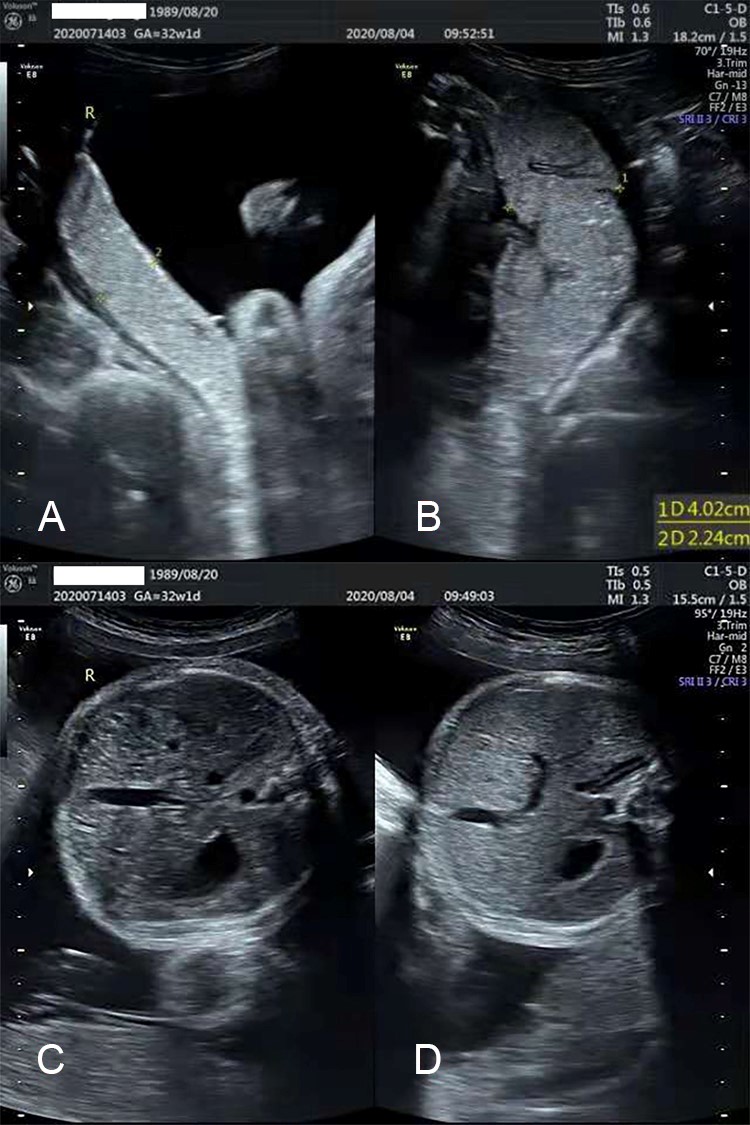

A 30-year-old woman (gravida 4, para 1) was referred to The First Affiliated Hospital of Xiamen University due to the suspicion of twin-twin transfusion syndrome (TTTS) at 29+2 weeks of gestation. Ultrasound examination revealed considerable amniotic fluid discrepancy between two fetuses, with the deepest vertical pocket (DVP) of amniotic fluid of 13.1 cm and 2.3 cm, respectively. Both twins had a visible bladder. Doppler measurements of the umbilical artery pulsatility index (PI) and middle cerebral artery (MCA) PI were normal and no MCA peak systolic velocity (PSV) discrepancy was found (1.14 MoM of recipient and 1.25 MoM of donor). TTTS stage I was diagnosed. The patient was administered two doses of intramuscular dexamethasone 6 mg given 12 h apart. To alleviate patient’s abdominal pain and dyspnea caused by polyhydramnios, amnioreduction was performed at 29+4 gestational weeks. 4800 mL of amniotic fluid from the recipient’s sac was drained within 30 min, resulting in DVP of 7.3 cm in the recipient’s sac. Subsequent ultrasound examination at day 1 after amnioreduction showed an increased DVP of 3.4 cm in the donor and a decreased DVP of 8.9 cm in the recipient. The MCA PSV was normal for both twins (1.13 MoM of donor and 1.08 MoM of recipient). At day 3 after amnioreduction, MCA PSV discrepancy was noted with 64.5 cm/s (1.59 MoM) in the donor and 43.9 cm/s in the recipient (1.09 MoM). DVP of the donor twin was 2.1 cm and that of the recipient twin was 9.5 cm. Afterwards, MCA PSV remained stable with 66.6 cm/s in the donor (1.57 MoM) and 41.5 cm/s in the recipient (1.11 MoM). DVP of the donor twin was 3.2 cm to 5.0 cm and that of the recipient twin was around 10 cm. None of the placental dichotomy, cardiomegaly of the donor and starry-sky liver of the recipient was present. 18 days after amnioreduction (gestational 32+1 weeks), she had chest tightness, abdominal distension and was unable to lie down. DVP was 10.1 cm for the recipient and 6.1 cm for the donor. The MCA PSV discrepancy was similar as before with 66.33 cm/s in the donor (1.49 MoM) and 4.47 cm/s in the recipient (1.0 MoM). However, placental dichotomy (Figure 1), starry-sky liver of the recipient (Figure 2) and small amount of right pleural effusion of donor were noted. The recipient’s placenta was hypoechoic and thickened 2.2 cm, while the donor’s placenta was hyperechoic and thickened 4.6 cm. TAPS was diagnosed. The doner had no cardiomegaly. Though the MCA PSV discrepancy was not severe, considering the whole image, the stage of TAPS might be higher than stage I, thus caesarean section was performed. At birth, the recipient twin (birthweight 2070 g, APGAR score 8–9–9) was severely plethoric with hemoglobin concentration of 22.2 g/dL, while the donor (1700 g, APGAR score 8–9–9) was anemic with hemoglobin level of 9 g/dL, which met the diagnostic criteria of stage Ⅱ TAPS. The skin color of the twins at birth is shown in Figure 3. The placental mass was plethoric of the recipient and pale of the donor. Placental injection was tried but not very successful, but it still revealed 3 anastomosis of tiny blood vessels arteriovenous without arterioartery anastomosis. The recipient twin received partial exchange blood treatment and the donor twin received blood transfusion. No other abnormalities were detected and the twins were discharged from hospital without complications.

Figure 2. The difference in placental thickness is shown here. A: recipient, B: donor. Starry-sky liver of the recipient and small amount of right pleural effusion of donor. C: recipient, D: donor.